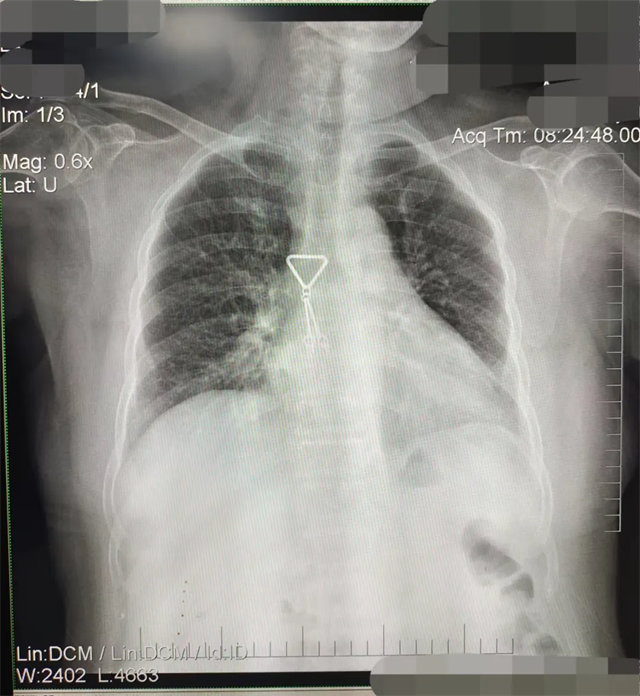

缺陷:兩肩胛骨未拉開(kāi)肺野之外,吸氣不完全,且存在金屬飾品遮擋。

解決:去除金屬飾品及內(nèi)衣后重新按標(biāo)準(zhǔn)體位攝片即可。